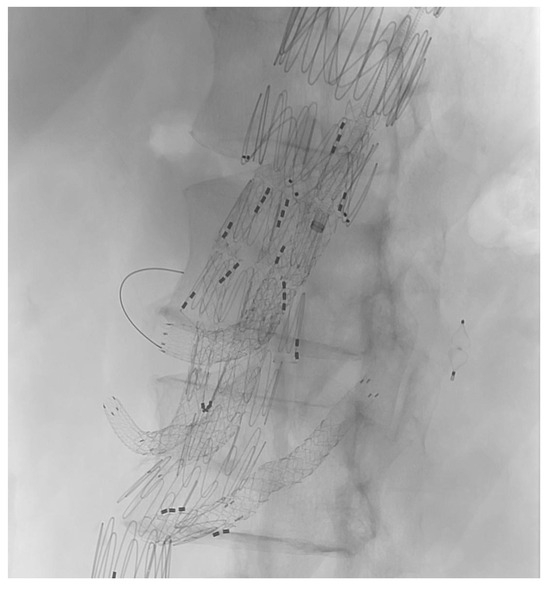

Every patient received a preprocedural thin-slice computed tomography angiography (CTA), and the measurement and planning of the devices was performed by the operating vascular surgeon in cooperation with the custom-made device planning center from Cook (Bloomington, IN, USA) (Figure 1). This multidisciplinary approach ensures an optimal device fit and minimizes the risk of procedural complications.

Figure 1. Planning of a custom-made device with one upward-facing branch.